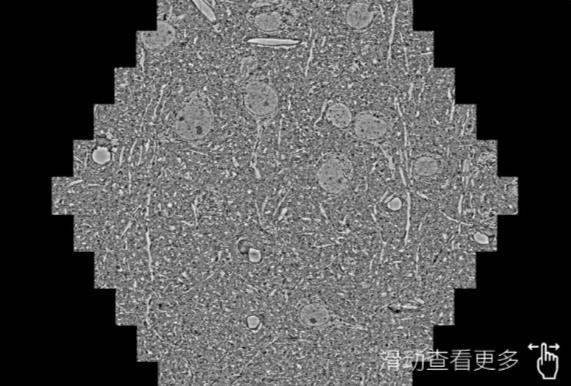

鼠脑切片。左图使用德阳蔡司德阳扫描电镜MultiSEM706对165μmx143pm面积区域成像,耗时仅需1.5秒。右图为鼠脑切片中30μm区域放大效果。样品由芝加哥大学B.Kasthuri提供。

使用蔡司高速德阳扫描电镜MultiSEM对1mm²人脑皮层组织进行高分辨成像,并对其中的各种细胞结构进行三维重构分析。左图展示了2x3mm²组织平面中锥体神经元的三维重构效果。右图显示了局部体积神经元三维重构。图像由哈佛大学chtman实验室提供,渲染图由D. Berger 制作。